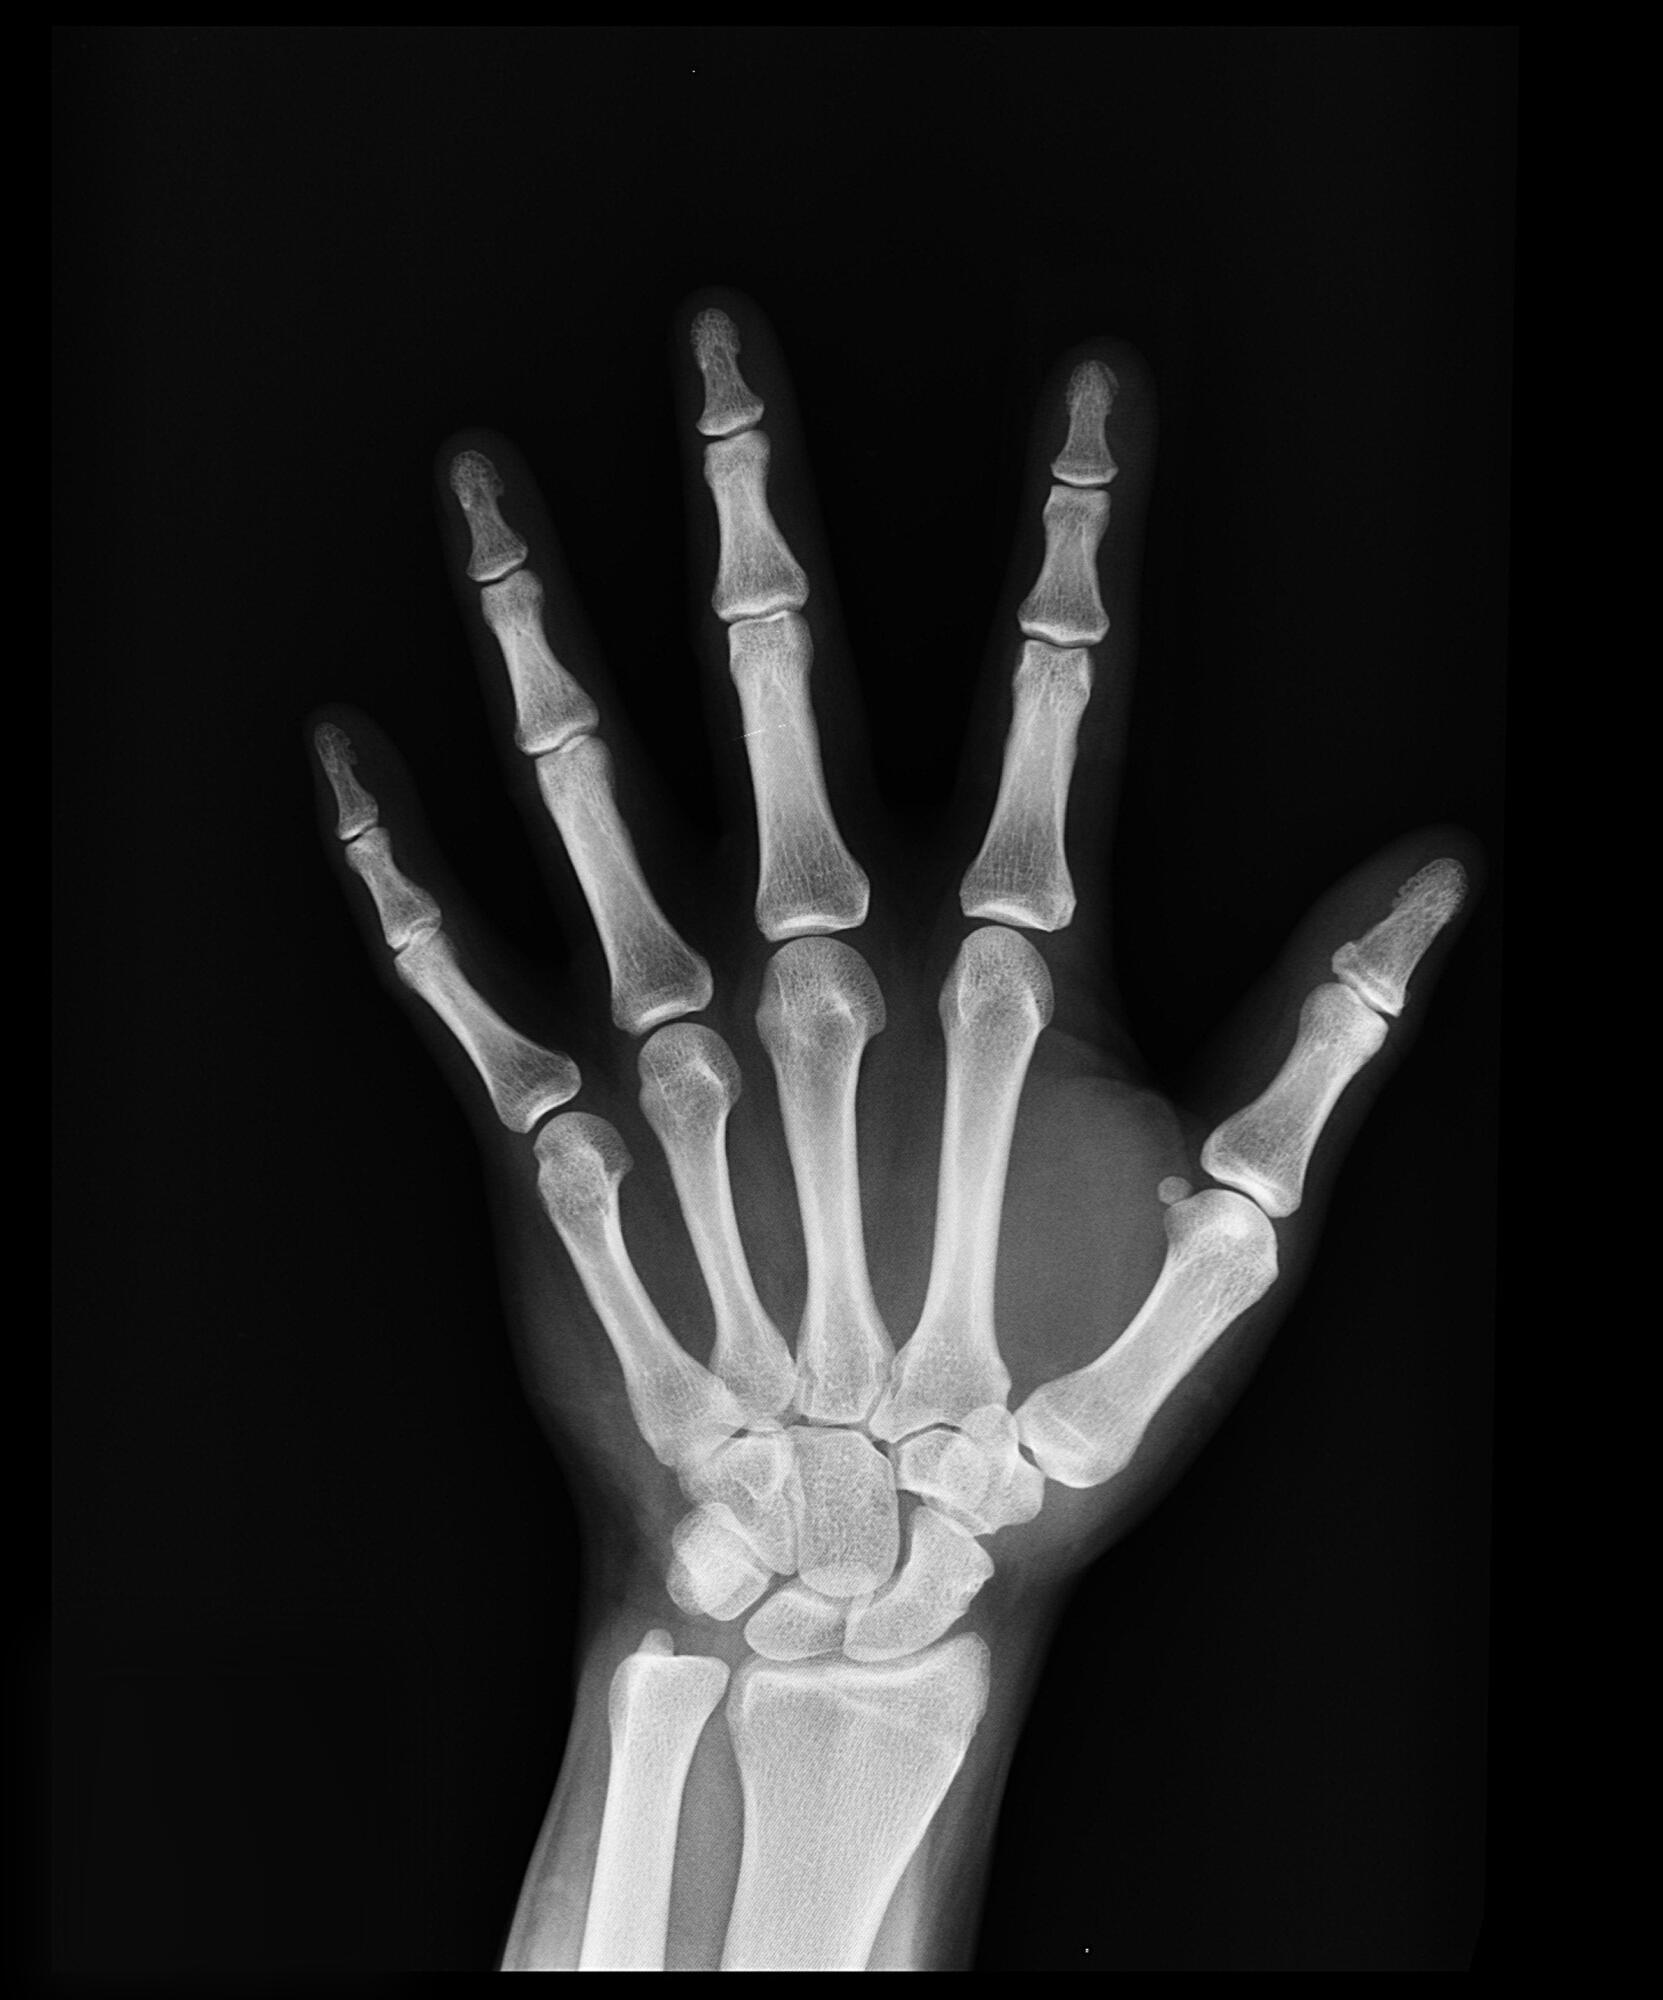

Yes, most urgent care centers provide X-ray services. This makes it easier for you to receive a quick diagnosis and treatment without the hassle. These facilities are designed to handle a variety of non-life-threatening conditions that require imaging, including the following:

• Sprains and fractures

Many urgent care centers now use digital X-ray technology, which provides faster results and clearer images. This allows doctors to assess your condition quickly and recommend the appropriate treatment. If you need an imaging service, call ahead to confirm whether your nearest urgent care center offers x-ray services.